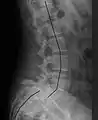

![]() Radiografía de la columna lumbar lateral con una anterolistesis de grado III en el nivel L5-S1. | ||

Clasificación por grado de deslizamiento, medido como porcentaje del ancho del cuerpo vertebral:[14] La espondilolistesis de grado I representa aproximadamente el 75 % de todos los casos.[15]

- Grado I: 0–25%

- Grado II: 25- 50%

- Grado III: 50–75%

- Grado IV: 75–100%

- Grado V: superior al 100%